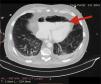

A 72-year-old man, previously independent, was admitted to the emergency department following cardiorespiratory arrest. A chest computed tomography scan (CTS) was requested. During the exam, the patient experienced sudden hypotension (65/20¿;mmHg) and poor peripheral perfusion. The exam was suspended and a fluid bolus was administered, resulting in transient reversal of the condition. Gas was detected in the injection system, which was replaced, and the exam was repeated. The CTS revealed gas embolism with an air-fluid level in the main pulmonary artery (marked with an arrow in Fig. 1), right atrium and right ventricle (marked with an arrow in Fig. 2), as well as in the left upper lobar artery (marked with an arrow in Fig. 3). Due to the venous gas embolism, he was transferred for treatment at a hyperbaric medicine center.